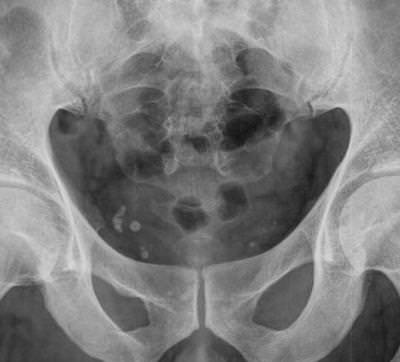

Образование флеболитов может идти в любых достаточно крупных венозных сплетениях, однако чаще всего их находят в венах малого таза. В этой статье мы будем рассказывать про данные образования в целом на примере флеболитов вен малого таза. Подобные образования можно встретить также в венозных стволах нижних конечностей и внутренних органов.

Флеболитиаз вен малого таза – чаще всего «женское» состояние, у мужчин эти образования в малом тазу встречаются значительно реже.

Часто обнаружение флеболитов – совершенно неожиданная находка при рентгенологических или томографических исследованиях, реже их можно обнаружить при ультразвуковых исследованиях. Обычно подобные образования являются случайным открытием и никак не беспокоят пациента. Называть флеболитиаз заболеванием в корне неверно, поскольку это явление совершенно безопасно.

Локализация флеболитов в малом тазу

Образование флеболитов в малом тазу у женщин и мужчин имеет много общего.

Флеболиты таза представляют собой кровяной сгусток, который со временем превратился в камень за счет пропитывания солями кальция. Чаще всего не дает клинической симптоматики, обнаруживается у женщин при прохождении рентгенологического обследования. Внешний вид таких образований нередко ошибочно расценивается как камень мочеточника, почек или мочевого пузыря.